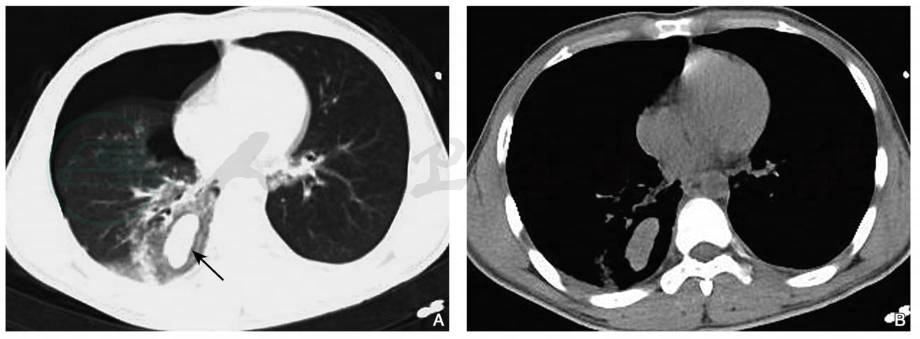

图2肺裂伤

男性,38岁,胸部CT平扫肺窗(A、B)显示双肺野内见多发斑片状高密度影,左肺下叶为著。左侧胸腔内见局限性无肺纹理透亮区(箭)。同层纵隔窗(C、D)显示双侧胸腔积液,双侧胸膜增厚及心包积液。注:环形致密影为支架管

引自:中华影像医学·呼吸系统卷.第3版.ISBN:978-7-117-28903-0.主编:

(A)示双下肺膨胀不全,左侧气胸;治疗后1周复查(B)示双下肺实变影,左侧少许气胸。为治疗后2周复查

(C)示右下肺胸膜下残留少许斑片状及条索状高密度影